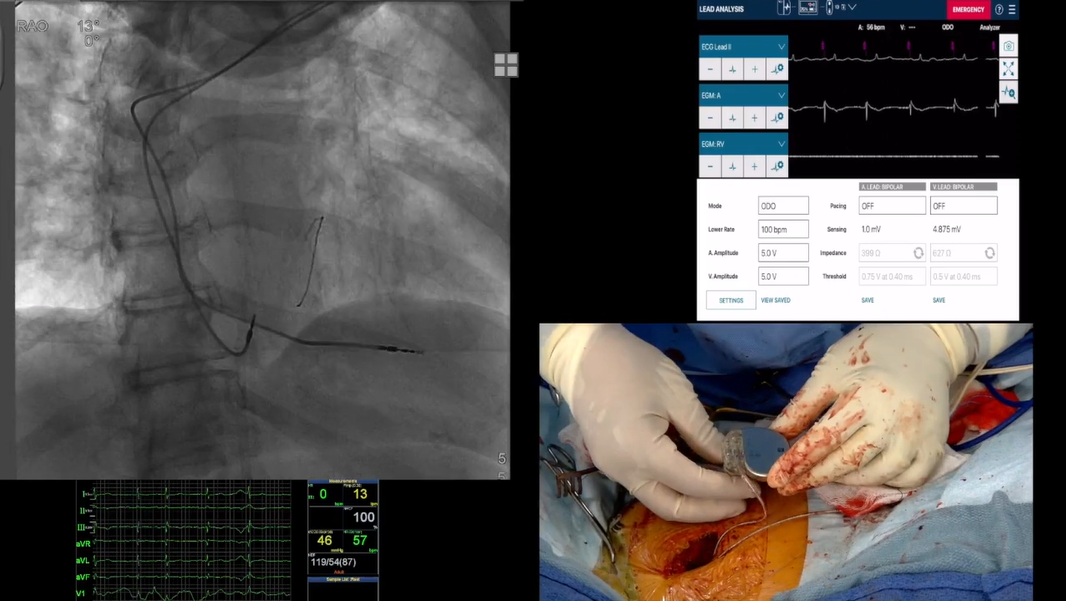

• Interpret fluoroscopic imaging for procedural accuracy